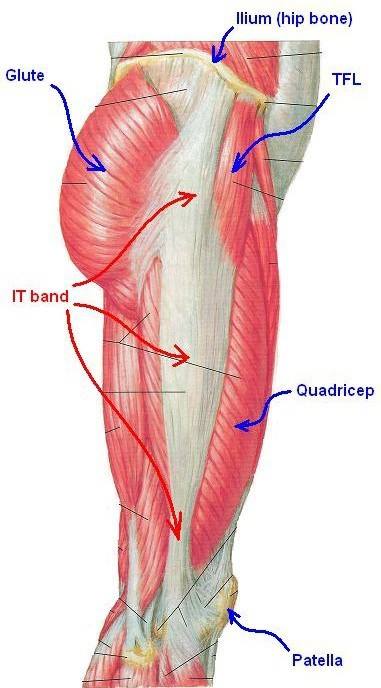

This bursa is at the top, outer side of the femur. It has the function of working as a shock absorber and as a lubricant for the movement of the muscles adjacent to it, especially the Ilio-Tibial Band (ITB). This is a strong sheet of tissue that runs from the Pelvis all the way past the knee to insert into the Tibia.

The ITB can get tight over time or due to general deconditioning and poor gait. The ITB will cause friction over the Trochanteric Prominence causing the Bursa to get inflamed.